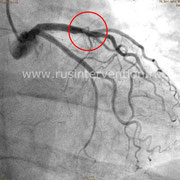

Пациент К., 70 лет, боли за грудиной, чувство нехватки воздуха при физической нагрузке, максимальные цифры артериального давления до 180/90 мм рт.ст., результат нагрузочной пробы (Тредмил-Теста) – проба сомнительная (типичный болевой приступ за грудиной, без изменений на ЭКГ).

Больному проводится коронарография, где выявлен стеноз одной из коронарной артерии около 30-40%, далее этому пациенту определяется ФРК и оказывается, что пограничный стеноз является значимым и требует стентирования, что полностью несоответствует ангиографической картине.

Сравнение коронарографии и коронарографии совместно с определением фракционного резерва кровотока

Данный пример еще раз показывает значимость и необходимость проведения дополнительных диагностических методов в дополнении к стандартной коронарографии.